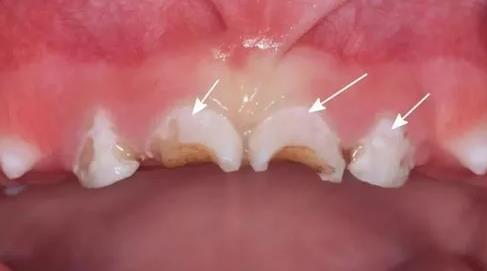

1,齲齒

牙齒缺鈣是會(huì)引起牙齒內(nèi)出現(xiàn)齲洞,嚴(yán)重的齲洞還會(huì)導(dǎo)致牙齒內(nèi)發(fā)生炎癥,甚至還會(huì)引起牙齒出血,牙齦紅腫等。一旦出現(xiàn)齲齒的話,應(yīng)該及時(shí)調(diào)節(jié),才能夠預(yù)防。

3,出現(xiàn)白色斑塊

牙齒如果缺乏鈣的話,會(huì)導(dǎo)致牙齒外形發(fā)育不良,在牙齒表面是會(huì)容易出現(xiàn)白色斑點(diǎn)的,甚至?xí)鹧烙再|(zhì)脫落,導(dǎo)致牙釉質(zhì)與牙本質(zhì)的結(jié)合不緊密。

4,牙齒變黃

牙齒缺鈣是會(huì)引起牙齒變色,容易造成牙齒發(fā)黃,久而久之會(huì)引起牙齒敏感 引起各類(lèi)牙齒疾病。